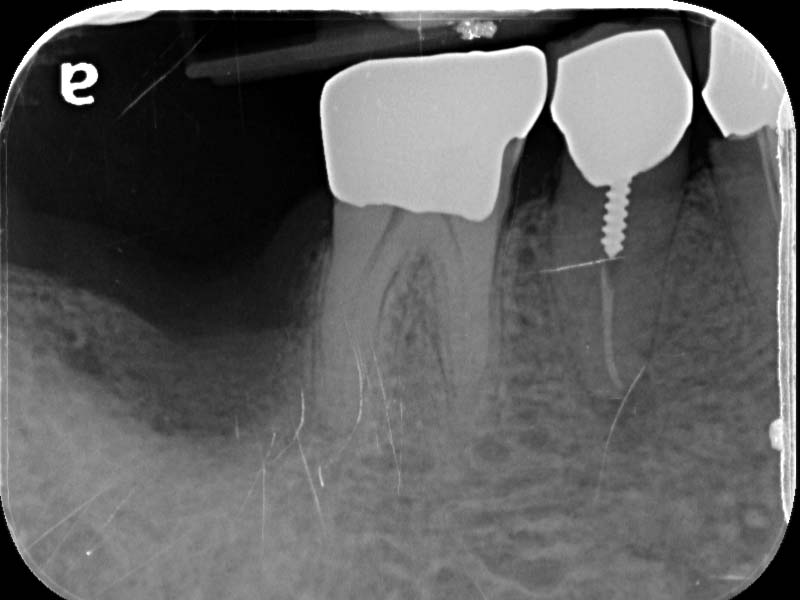

圖例為案例分享:

帳棚釘+骨粉+再生膜術後7個月

植牙當日